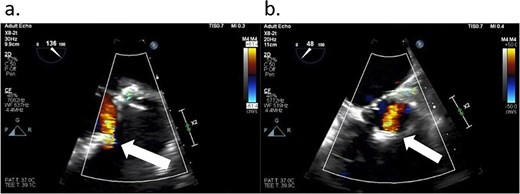

After the aortic cross-clamp was removed, transesophageal echocardiogram (TEE) demonstrated what was suspected to be a mild-to-moderate paravalvular leak along the non/right coronary cusp commissure. The jet appeared highly eccentric and perpendicular to the flow of the left ventricular outflow tract (Fig. 1). Given the size of the leak, it was decided to rearrest the heart. After reopening the aortotomy and assessing the bioprosthesis, no valve defects were seen. But given the suspected friable and thin annular tissue, the base of the aorta was further reapproximated and reinforced to the external sewing ring at the right/noncoronary commissure with multiple prolene, pledgeted sutures. After the second cross-clamp was removed, TEE demonstrated a larger, now broad-based, moderate or greater regurgitant leak at the non/right commissure, and, in addition, the presence of a new mild leak along the left/right commissure (Fig. 2). At this point, a transprosthetic leak was suspected with potential malfunction of the valve. The heart was rearrested for a third time, and the bioprosthetic valve was reexamined and annulus probed. The valve was explanted without any annular pathology being evident, and examination of the valve on the back table demonstrated a torn area of cloth along the right/non and left/right commissures of the cuff at the level of the stent posts, suspected to be the site of the leaks (Fig. 3). A new same-sized 27 mm Inspiris Resilia valve was chosen, and the valve was placed on to the annulus in a supra-annular fashion with multiple ventricularly based 2-0 Ethibond EXCEL pledgeted mattress sutures, and secured with the COR-KNOT device.

TEE showing a leak (arrows) from the Inspiris Resilia valve in the aortic position after the first aortic cross-clamp was removed. (a) Long axis view. (b) Short axis view.